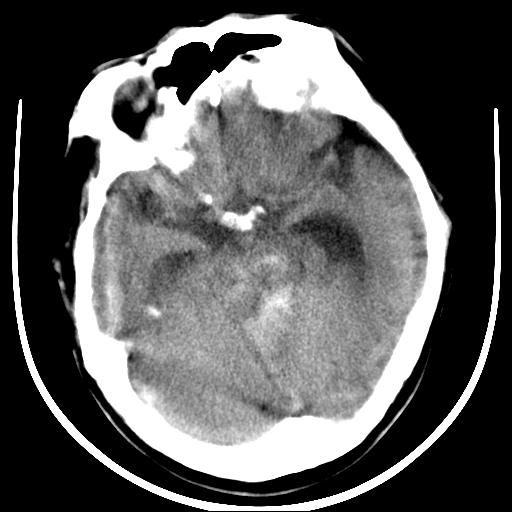

标题: CT16838:男58岁,意识不清2小时,请会诊出血部位该如何写。 [打印本页]

标题: CT16838:男58岁,意识不清2小时,请会诊出血部位该如何写。

呵呵  这样的做ct效果也太差了吧1首先 看见脑室扩大 1、左侧壳核出血。不足以解释临床的昏迷。

1)脑干、左侧桥小脑臂及小脑蚓部出血破入蛛网膜下腔。2)左侧基底节区灶性出血,不排除钙化灶。3)脑室系统少量积血。4)脑积水。

(患者病情危重,出现不自主运动——是引起图像质量不佳的主要原因)

脑干左侧原发性脑出血破入脑室系统及蛛网膜下腔出血伴梗阻性脑积水。左侧基底节区原发性脑出血。脑萎缩。